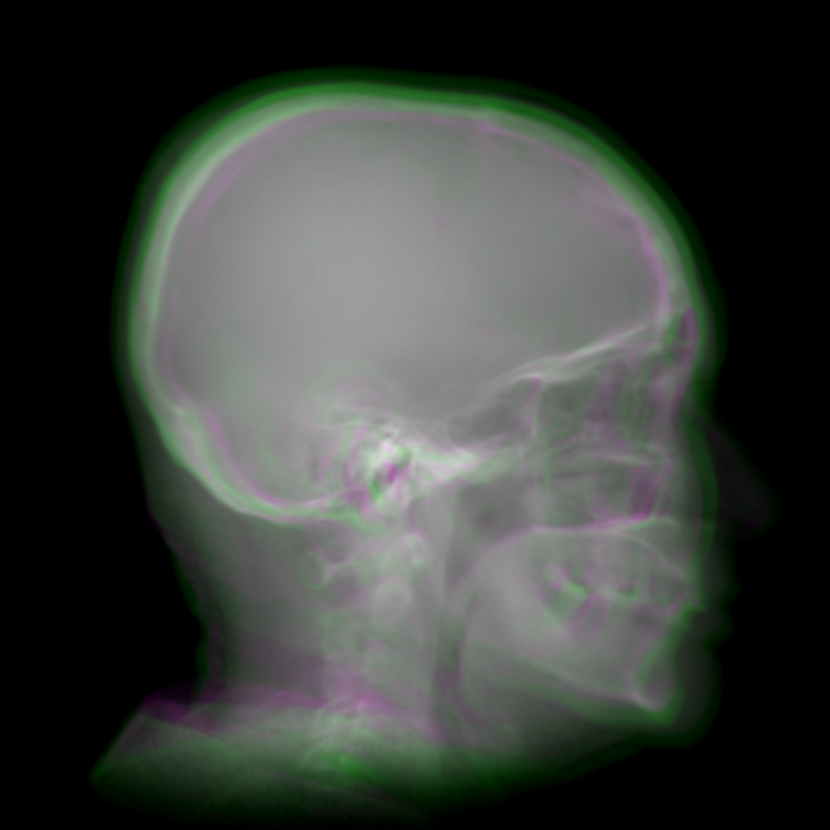

To combine such dual projection information, we convert the patches from 0superscript00^{\circ} and 180superscript180180^{\circ} cone-beam projections to 3-channel patches forming RGB color patches. The 0superscript00^{\circ} patch is used for the red and blue channels, while the 180superscript180180^{\circ} patch is used for the green channel. The 0superscript00^{\circ} patch instead of the 180superscript180180^{\circ} patch takes two channels, since the target cephalograms are also acquired in the 0superscript00^{\circ} view in our setting. In the RGB patch, the intensity difference between the 0superscript00^{\circ} patch and the 180superscript180180^{\circ} patch is revealed by the color: grey areas have the same values for the three channels, indicating that the intensity values from the 0superscript00^{\circ} and 180superscript180180^{\circ} patches respectively are close to each other, while green areas indicate that the 180superscript180180^{\circ} patch has larger values and magenta areas indicate that the 0superscript00^{\circ} patch has larger values. An example is displayed in Fig. 5, where Figs. 5(a) and (b) are the 0superscript00^{\circ} and 180superscript180180^{\circ} patches respectively, Fig. 5(c) is the RGB patch as the input of the neural network, and Fig. 5(d) is the corresponding target output of the neural network.

Refer to caption

(a) 0superscript00^{\circ} CBCT projection

(b) 180superscript180180^{\circ} CBCT projection

(c) RGB input patch

(d) Target patch

Fig. 5: One patch example for dual projections to one cephalogram synthesis: (a) the first quadrant patch from the 0superscript00^{\circ} rebinned cone-beam projection; (b) the first quadrant patch (horizontally flipped) from the 180superscript180180^{\circ} rebinned cone-beam projection; (c) the RGB patch using (a) for the red and blue channels and (b) for the green channel, where the colourful areas highlight the difference between (a) and (b); (d) the target patch synthesized by our proposed volume-to-cephalogram method.